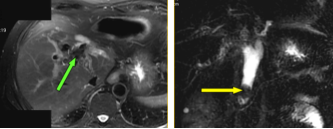

(3)腺囊性肿瘤:浆液性囊腺瘤常发生在胰腺体尾部,老年女性多见。切面呈蜂窝状;黏液性囊腺瘤和囊腺癌,黏液性囊腺瘤常有恶变的可能,实际上潜在的恶性肿瘤。胰体尾部多见,肿瘤常常很大,为单囊或几个大囊组成。

截屏2022-10-06 19.01.50

胰腺黏液性囊腺瘤

截屏2022-10-06 19.02.15

胰腺浆液性囊腺瘤